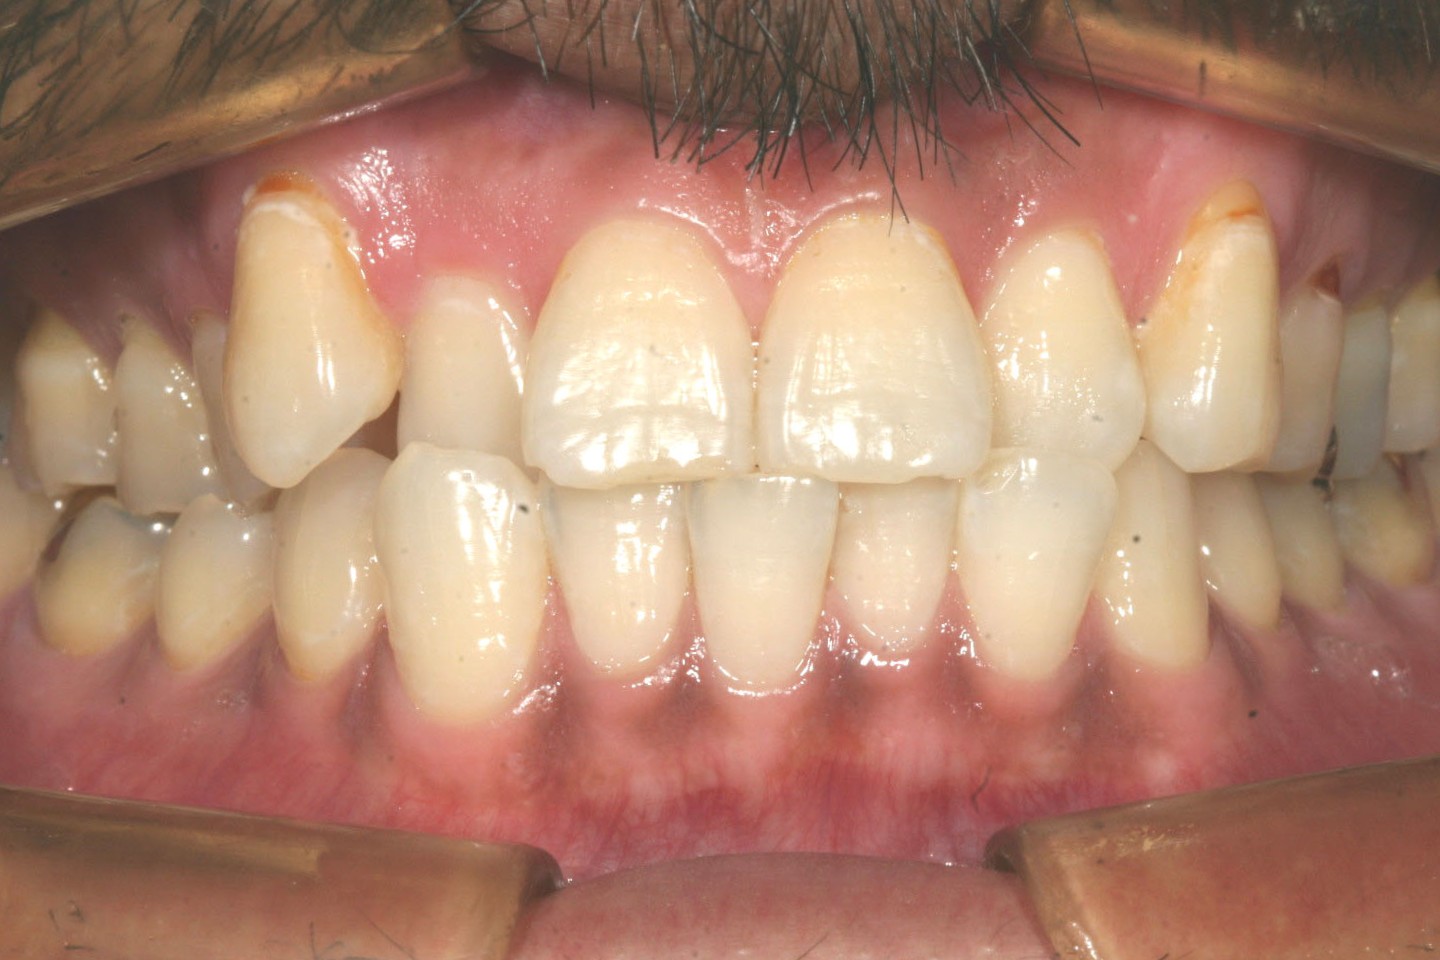

右の犬歯の突出が目立ちます。

側面感は問題無さそうです。